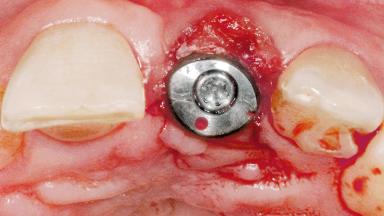

Late Flapless Placement of an Implant in a Maxillary Left Central Incisor Site

A 39-year-old male patient presented with a chief complaint of discomfort and gingival discoloration around his maxillary left central incisor. He was in good general health and was a non-smoker. His past dental history was significant because of the traumatic fracture of tooth 21 in a sporting accident at age 13. Initial dental treatment included endodontic therapy and a full-coverage restoration. The patient became symptomatic 5 years later, when structural failure of the tooth resulted in the dislodgment of the crown. Endodontic retreatment, apical surgery, and post-and-core restoration were performed.

Type of Implants One-Piece

Placement Protocol Early or late implant placement